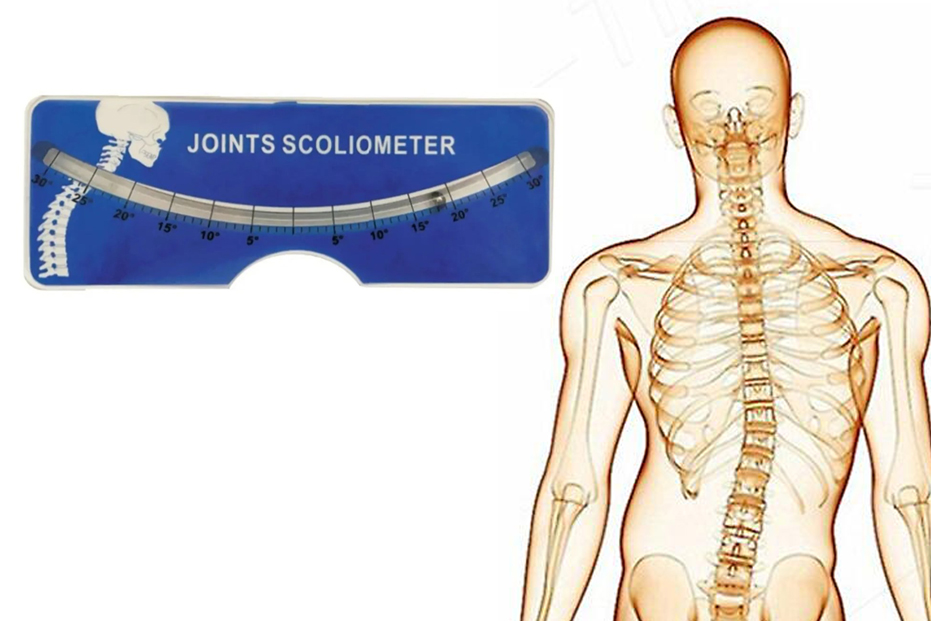

Ftrmalzemecim.com’da; egzersiz ekipmanlarından elektroterapi cihazlarına, sıcak-soğuk uygulama ürünlerinden yürüteç, baston ve tekerlekli sandalye gibi yardımcı ekipmanlara kadar geniş bir ürün yelpazesi bulunmaktadır. Ürünlerimiz, uzman fizyoterapistler tarafından test edilmekte ve klinik kullanıma uygunluğu onaylanarak satışa sunulmaktadır. Her biri Sağlık Bakanlığı onaylı, kaliteli ve güvenilir ürünlerdir.

Yeni bir fizik tedavi merkezi kurmayı planlayan fizyoterapistlere A’dan Z’ye klinik kurulum danışmanlığı sunmaktayız. Gerekli ekipman listesinin oluşturulmasından yönetmeliklere uygun ürün seçimine kadar tüm süreçlerde profesyonel destek sağlıyoruz. Güncel mevzuatı yakından takip eden uzman kadromuzla, sadece ürün değil, bilgi ve çözüm de sunuyoruz.